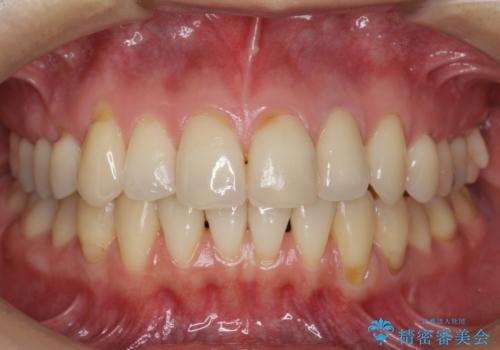

埋まっていた歯をしっかり引っ張り出すことができ、また、前歯の見た目も非常に良くなりました。

ワイヤー矯正を奥歯の部分的に行なっただけで、治療の大半をマウスピース矯正で行うことができ、非常に喜んでいただきました。

また、左上の変色した前歯はセラミックでやりかえを行なっています。